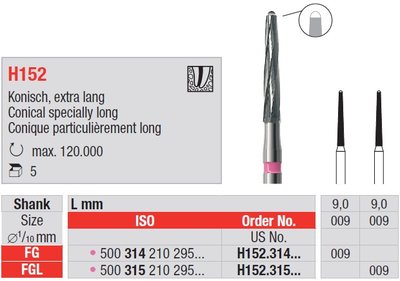

Edenta H152 - endodontické nástroje, extra dlhý kónus Endobur - 5 ks

EdentaBalení: 5 ks

Balení: 5 ks

| Značka | Edenta |

| SKU | EDE H152.314.009 |

| Kategorie | Ordinace > Endodoncie > Endo nástroje > Kořenové nástroje > H-File (Protahováčky Hedström) |